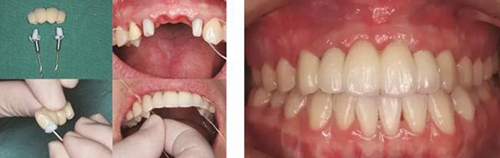

(4)2015年3月—2015年12月:早期修復(fù)伴軟組織誘導(dǎo)成形對(duì)患者制取開窗印模后,使用橋用金屬臨時(shí)基臺(tái),制作聚甲基丙烯酸甲酯(PMMA,登士柏公司,德國)經(jīng)CAD/CAM切削的臨時(shí)修復(fù)橋體,戴入臨時(shí)修復(fù)體對(duì)牙齦軟組織進(jìn)行誘導(dǎo)成形,采用動(dòng)態(tài)加壓技術(shù),最初緩慢戴入臨時(shí)修復(fù)體,撐開牙齦軟組織袖口,擠壓粘膜,粘膜受到擠壓后缺血變白,10min內(nèi)可恢復(fù)為粉紅色。臨時(shí)修復(fù)體為縱向螺絲固位,便于拆卸調(diào)改形態(tài),囑患者勿用臨時(shí)修復(fù)體咬物,注意口腔衛(wèi)生,用牙線或沖牙器等將種植體周圍清潔干凈,每月進(jìn)行復(fù)查,不斷調(diào)改臨時(shí)冠的穿齦形態(tài),讓出軟組織生長空間,直至誘導(dǎo)牙齦形成類似于天然牙的穿齦袖口形態(tài)。其中在早期修復(fù)3月時(shí),通過打開修復(fù)體間的三角間隙,以讓出齦乳頭生長的空間;在早期修復(fù)7月時(shí)對(duì)22位點(diǎn)唇側(cè)牙齦根方的軟組織增生物進(jìn)行刮除并縫合,同時(shí)將修復(fù)體的橋體部位調(diào)磨成卵圓形的蓋嵴部并高度拋光,以獲得良好的橋體部軟組織形態(tài),形成健康、連續(xù)且協(xié)調(diào)的軟組織輪廓。

圖17 CBCT測量骨量變化 圖18 早期修復(fù)戴牙當(dāng)天

圖21 早期修復(fù)3月 圖22 早期修復(fù)3月打開三角間隙

圖23 早期修復(fù)4月 圖24 早期修復(fù)7月切除軟組織增生后

圖25 早期修復(fù)7月調(diào)改橋體部形態(tài)為卵圓形并高度拋光 圖26 早期修復(fù)8月

圖27 早期修復(fù)8月調(diào)改后 圖28 早期修復(fù)10月

圖29 根管治療后的13行纖維樁修復(fù) 圖30 個(gè)性化轉(zhuǎn)移桿開窗取模

圖33 氧化鋯基底于口內(nèi)就位咬合正面觀 圖34 袖口正面觀

圖35 預(yù)粘接 圖36 戴入全瓷修復(fù)體正面觀

圖37 戴入全瓷修復(fù)體局部舌側(cè)觀 圖38 永久修復(fù)后微笑

圖39 永久修復(fù)后大笑